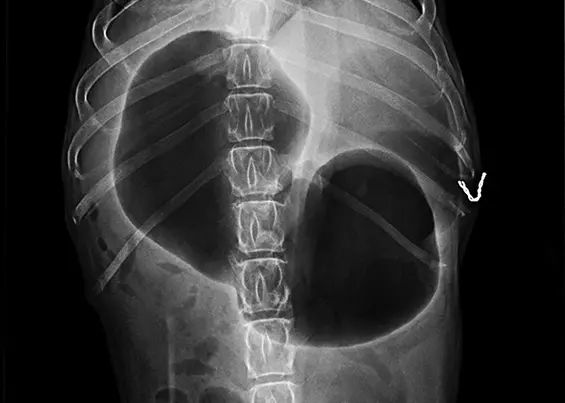

ROZSZERZENIE I SKRĘT ŻOŁĄDKA U PSÓW

Skręt żołądka to hasło, które spędza sen z powiek znakomitej części opiekunów dużych i olbrzymich ras. Zwłaszcza w gronie właścicieli molosów jest to temat, który notorycznie pojawia się zarówno na forach internetowych, jak i w rozmowach na żywo. Głośno wypowiedziany, zawsze wywołuje spore emocje, a wszystko za sprawą realnego zagrożenia życia, jakie za sobą niesie, oraz często nierównej walki z czasem.